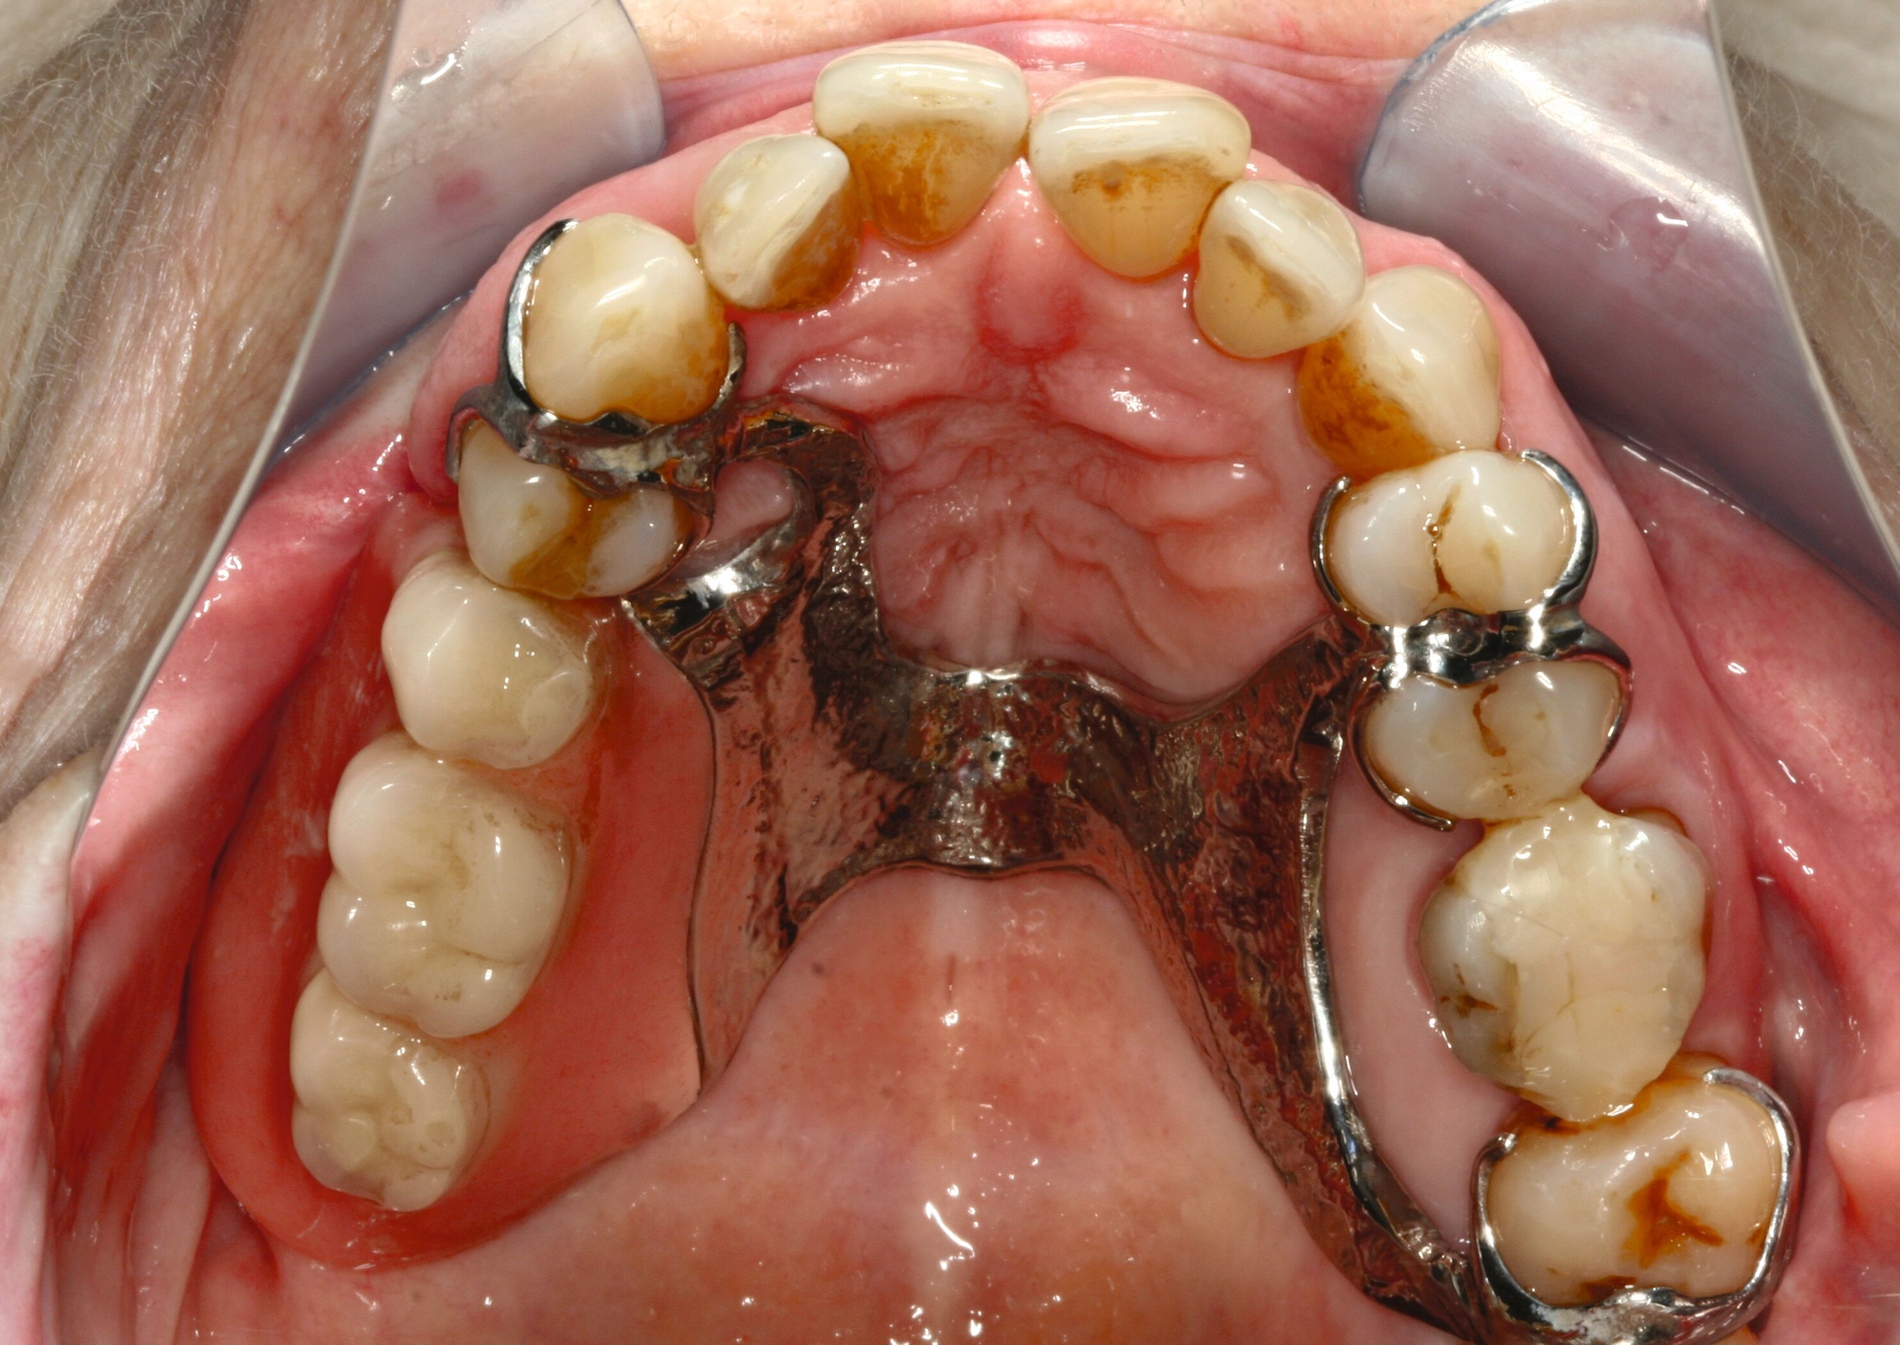

Eine 74-jährige Patientin erhielt eine Modellgussprothese im Oberkiefer zur Abdeckung einer Mund-Antrum-Verbindung infolge der Resektion eines malignen Befunds im Bereich des Alveolarfortsatzes rechtsseitig (Abbildung 1). Trotz mehrfacher Umarbeitungen gelang eine Adaption an den Zahnersatz nicht. Die Patientin empfand die Klammern als zu scharf und spitz. Zudem störte sie sich an der Ästhetik. Die Mundhygiene war gut, nur wenige Zähne besaßen eine Füllung. Es bestand eine hohe Erwartungshaltung an den Zahnersatz.

Bezogen auf die Belastbarkeit lagen zum damaligen Zeitpunkt trotz der Malignomtherapie keine Einschränkungen vor (BS 1). Dem Wunsch der Patientin nach einem Klammer-freien Zahnersatz konnte mit regulärem Therapieaufwand entsprochen werden (Abbildung 2). Nach dessen Eingliederung gelang eine rasche Gewöhnung. Die Patientin erschien viele Jahre regelmäßig zur professionellen Zahnreinigung und zur Kontrolle. Zahnmedizinische Interventionen waren nicht erforderlich.